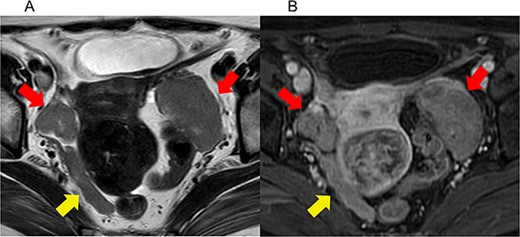

During her first visit, transvaginal ultrasonography revealed solid masses in both ovaries. Blood tests revealed unremarkable findings. Pelvic magnetic resonance imaging (MRI) revealed a mass measuring 2.3 cm in the right ovary and another one measuring 5 cm in the left ovary, both with a slightly high signal intensity on T2-weighted images and isointense with the myometrium on T1-weighted images, with smooth surfaces and homogeneous internal structures. There was also restricted diffusion, mild contrast enhancement, right external iliac lymph node enlargement, and disseminated mesenteric nodules (Fig. 1). CT revealed bilateral solid ovarian masses with mild contrast enhancement. The presence of multiple masses in the right pelvic cavity and mesentery suggested peritoneal dissemination. Positron emission tomography (PET-CT) revealed uptake in the ovaries and mesentery (Fig. 2). Upper and lower gastrointestinal endoscopy revealed unremarkable findings. Considerably, ovarian cancer with multiple metastases was suspected.

Imaging studies of pelvic magnetic resonance imaging (MRI). (a) Axial T2-weighted (T2WI) MRI, (b) axial contrast-enhanced T1-weighted (T1WI) MRI. The red arrows indicate bilateral ovarian tumors. The yellow arrows indicate pelvic dissemination. Bilateral ovarian masses exhibited a mildly hyperintense signal on T2WI and an isointense signal with the myometrium on T1WI. Both masses have a smooth surface and a homogeneous internal structure.